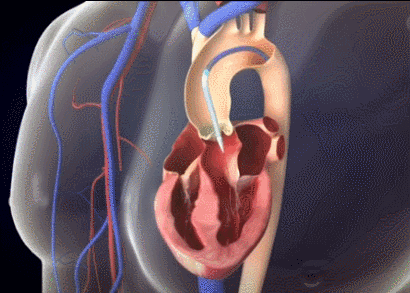

厦心急诊科主任王斌介绍,心脏血液进出有4个重要的阀门,都是瓣膜结构,其中就包括主动脉瓣和二尖瓣。心脏的血液经由主动脉瓣泵入主动脉,进而随着血管分支遍布全身。4个阀门中,主动脉瓣承受的压力最大,因而,主动脉瓣虽然耐用,但长年承受巨大压力还是容易坏掉。主动脉一旦狭窄,心脏的血液就无法顺利泵入主动脉供给全身,将造成严重后果。

但陈奶奶的情况要复杂疑难得多,经检查,她原有的二尖瓣机械瓣与主动脉瓣的位置距离仅2.7mm,一旦瓣膜植入位置不当,会影响原先二尖瓣瓣叶的正常开合,后果不堪设想,这给手术团队带来极大的挑战。

如何能更精准有效地将人工瓣膜微创植入主动脉瓣,且不影响二尖瓣机械瓣的运作呢?厦心王焱院长率团队进行了多次缜密术前讨论,最后决定为陈奶奶采用刚刚上市不久的新型人工瓣膜——可回收Venus A-Plus瓣膜。作为我国首个可回收瓣膜系统,该瓣膜能有效降低复杂手术难度,一旦瓣膜植入位置不合适,还可以回收后再次尝试,让医生在术中能更从容地进行精准定位释放,减少严重并发症的发生,从而降低手术风险,提高成功率。